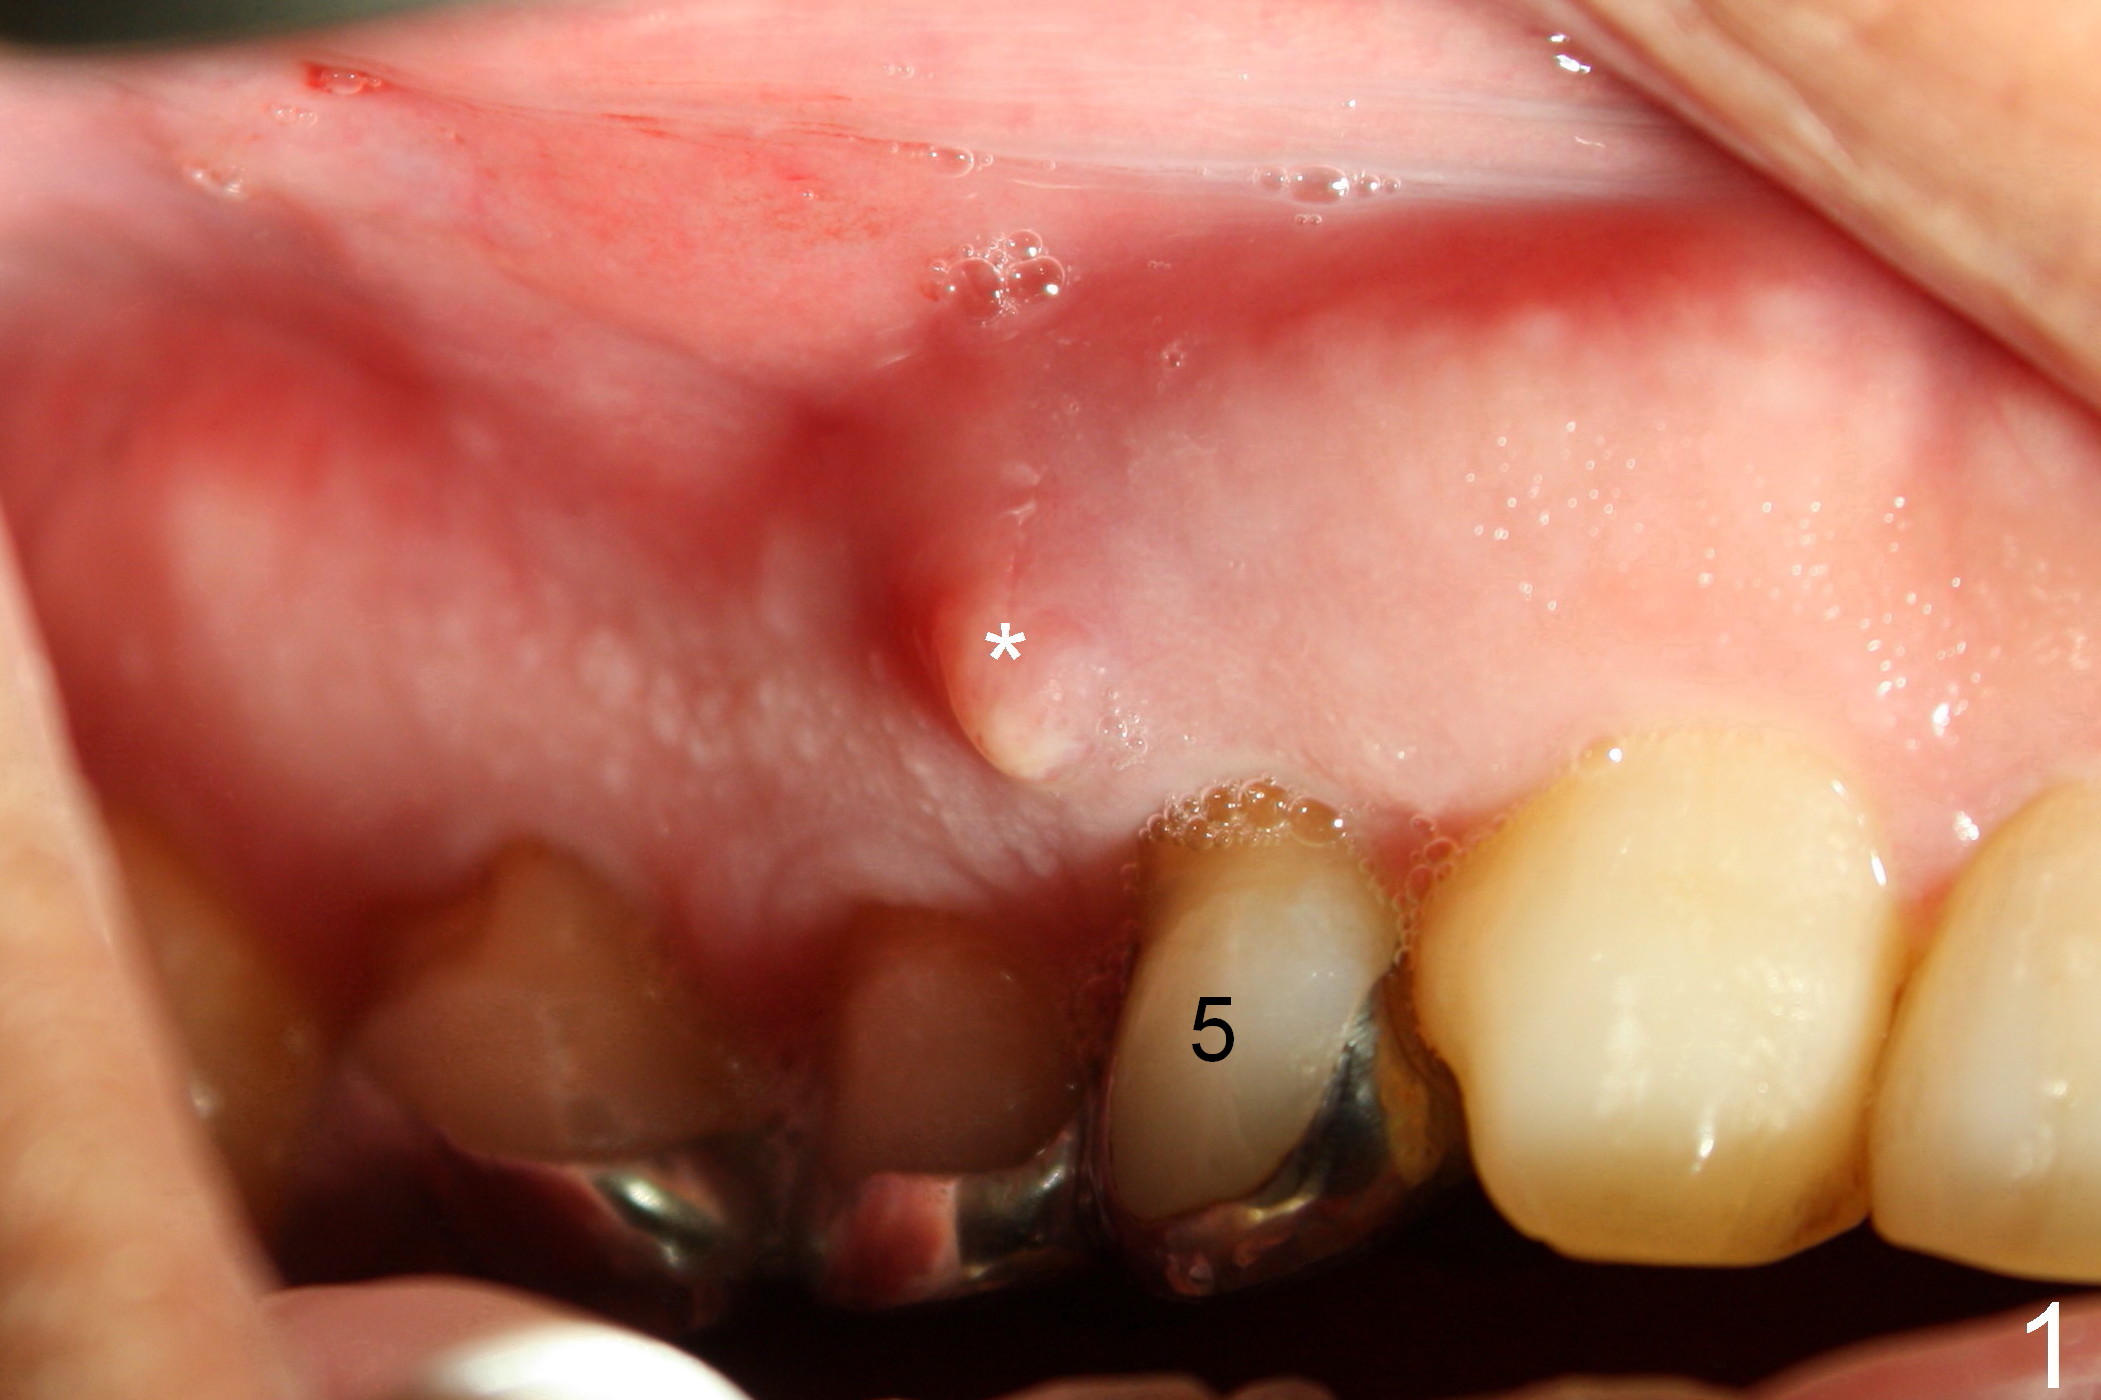

A 68-year-old man has pain and swelling associated with the tooth #5 (Fig.1). The fistula (*) is connected to the periapical radiolucency using a gutta percha (Fig.2 <). There are deep pockets distobuccal and lingual. The lingual root is found to have oblique fracture upon extraction. The distobuccal plate perforates (Fig.3). Collagen plug is placed. The buccal plate is concave (Fig.4) and socket density is low 2.5 months post extraction. Three months post extraction a 4.5x8 mm Bicon implant is placed after reamer and osteotome osteotomy (Fig.6). Bone density around the implant appears to increase 5 months post placement (Fig.7). Porcelain-fused-to-metal crown is cemented 2 weeks later. Bucco-occlusal porcelain chips 2 months post cementation. The patient decides to redo the crown. PA is taken before crown removal (Fig.8: 3 year 10 months post cementation). When a straight abutment is removed (Fig.9 A), a 15° angled abutment has to be used (Fig.10 red) for restoration.